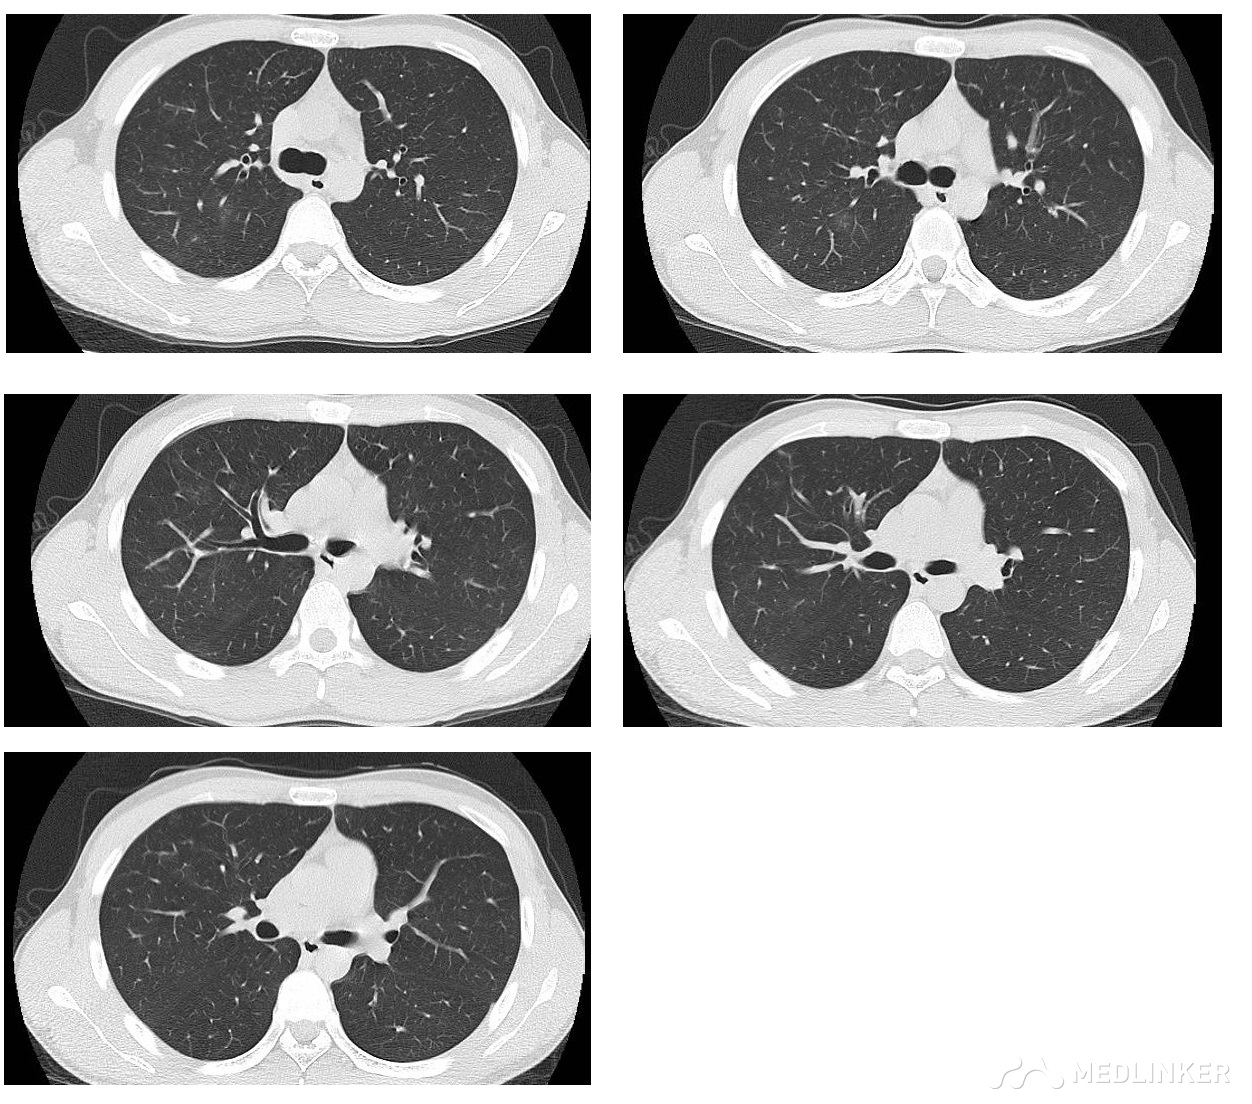

入院后完善相关检查:血常规五分类+CRP : WBC及NE 正常,单核细胞绝对值:0.82X10^9/L、单核细胞百分比:10.12%;生化全套:丙氨酸氨基转换酶(ALT):7U/L、门冬氨酸氨基转换酶(AST):13U/L、高密度脂蛋白C(HDL_c):0.82mmol/L、前白蛋白:196.7mg /L、总蛋白(TP):62.2g/L、转铁蛋白(TRF):1.840g /L、尿酸(URIC):513.3umol/L;降钙素原检查、DIC检查,ESR检查未见异常。肺炎组套示:支原体lgM阳性。食入物及吸入物变应原筛查:总IgE4级,余未见特殊。入院时胸部CT提示:右上肺斑片渗出影及类结节影,首先考虑炎症,需排除结核。

入院后结合病史,考虑支原体感染可能性大。依据如下:青年男性,双阶段病程,既往无过敏性鼻炎及哮喘病史,此次发病表现为气道高反应性,伴有胸闷,查体无异常,查血支原体lgM阳性,胸部CT虽然发生 在右上肺上叶尖后段,病灶呈多态性,有渗出,有类增殖病灶,但前段也有发生不支持。根据2016年支原体肺炎临床倾向性判断指南:①年龄<60岁 ②无或轻微基础疾病 ③持续或顽固性咳嗽 ④肺部体征不明显 ⑤无痰或通过快速诊断试验不能识别病原 ⑥外周血白细胞<10×109/L。而影像学可表现为:上肺野、双肺病灶,小叶中心性结节、树芽征、磨玻璃影以及支气管壁增厚,病情进展可呈实变 。据此,我们判断为支原体肺炎,而予拜复乐0.4g ivgtt qd 治疗10天后复查胸部CT,如下: